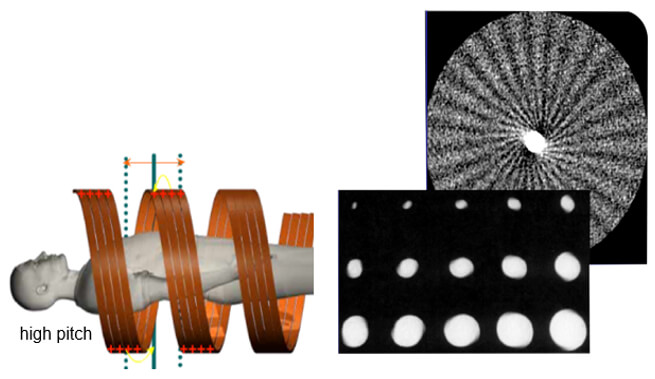

Temporal resolution is an indication of a CT system’s ability to freeze motions of the scanned object. Several factors influence the temporal resolution. The key factors are the gantry rotation time, acquisition mode, type of image reconstruction, and the pitch.

The concept of temporal resolution is fundamental to cardiac CT and MRI, in which a rapidly beating heart is imaged over the order of milliseconds into multiple frame-captures. The most straightforward way to reduce or eliminate the motion impact is to increase the scan speed.

Helical Artifact

Helical artifacts can sometimes be seen with faster scanning techniques. In general, the same artifacts are seen in helical scanning as in sequential scanning. However, there are additional artifacts that can occur in helical scanning due to the helical interpolation and reconstruction process. The artifacts occur when anatomic structures change rapidly in the z-direction (ie, at the top of the skull) and are worse for higher pitches. Helical and multisection technique artifacts are produced by the image reconstruction process.

This set of artifacts shows a fast anatomical variation in the Z direction.

Cone-Beam Artifact

When the collimation is greater than the Z-axis, the detectors will receive less information. This distorts the image during the tube rotation. When mathematical algorithms are used the artifact can be corrected. High collimation highlights the cone-beam artifacts.